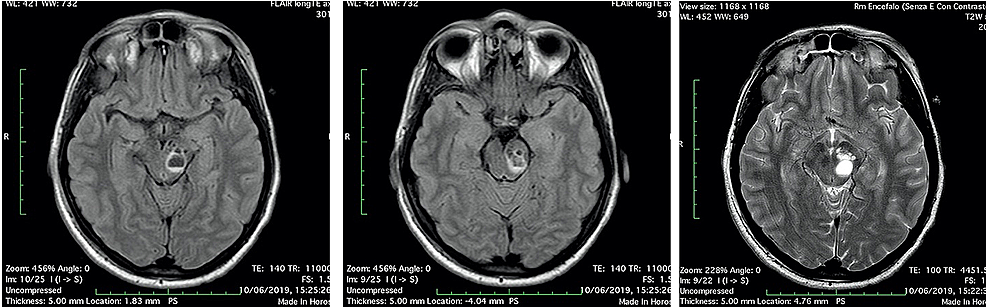

The first day after surgery, the patient was transfunded for hemoglobin 6.8 g/dL (normal range 12-16 g/dL), referring to scalp surgery. She complained headache, vertigo, nausea and diplopia, reflecting an involvement of the brainstem and the oculomotor nerves. A second CT and brain MRI with IV contrast were performed: CT scan showed a fluid-fluid level, with enlargement of left cerebral peduncle and a slight mass effect (Figure 2). MRI scan confirmed the same findings of fluid-fluid level, with enlargement of left cerebral peduncle and a slight mass effect; no contrast enhancement was observed: these findings were referred to enlargement of VRSs with post-traumatic bleeding. Neither SAH nor intracerebral hematomas were revealed (Figure 3). No neurosurgery was indicated but only clinical and imaging follow up.